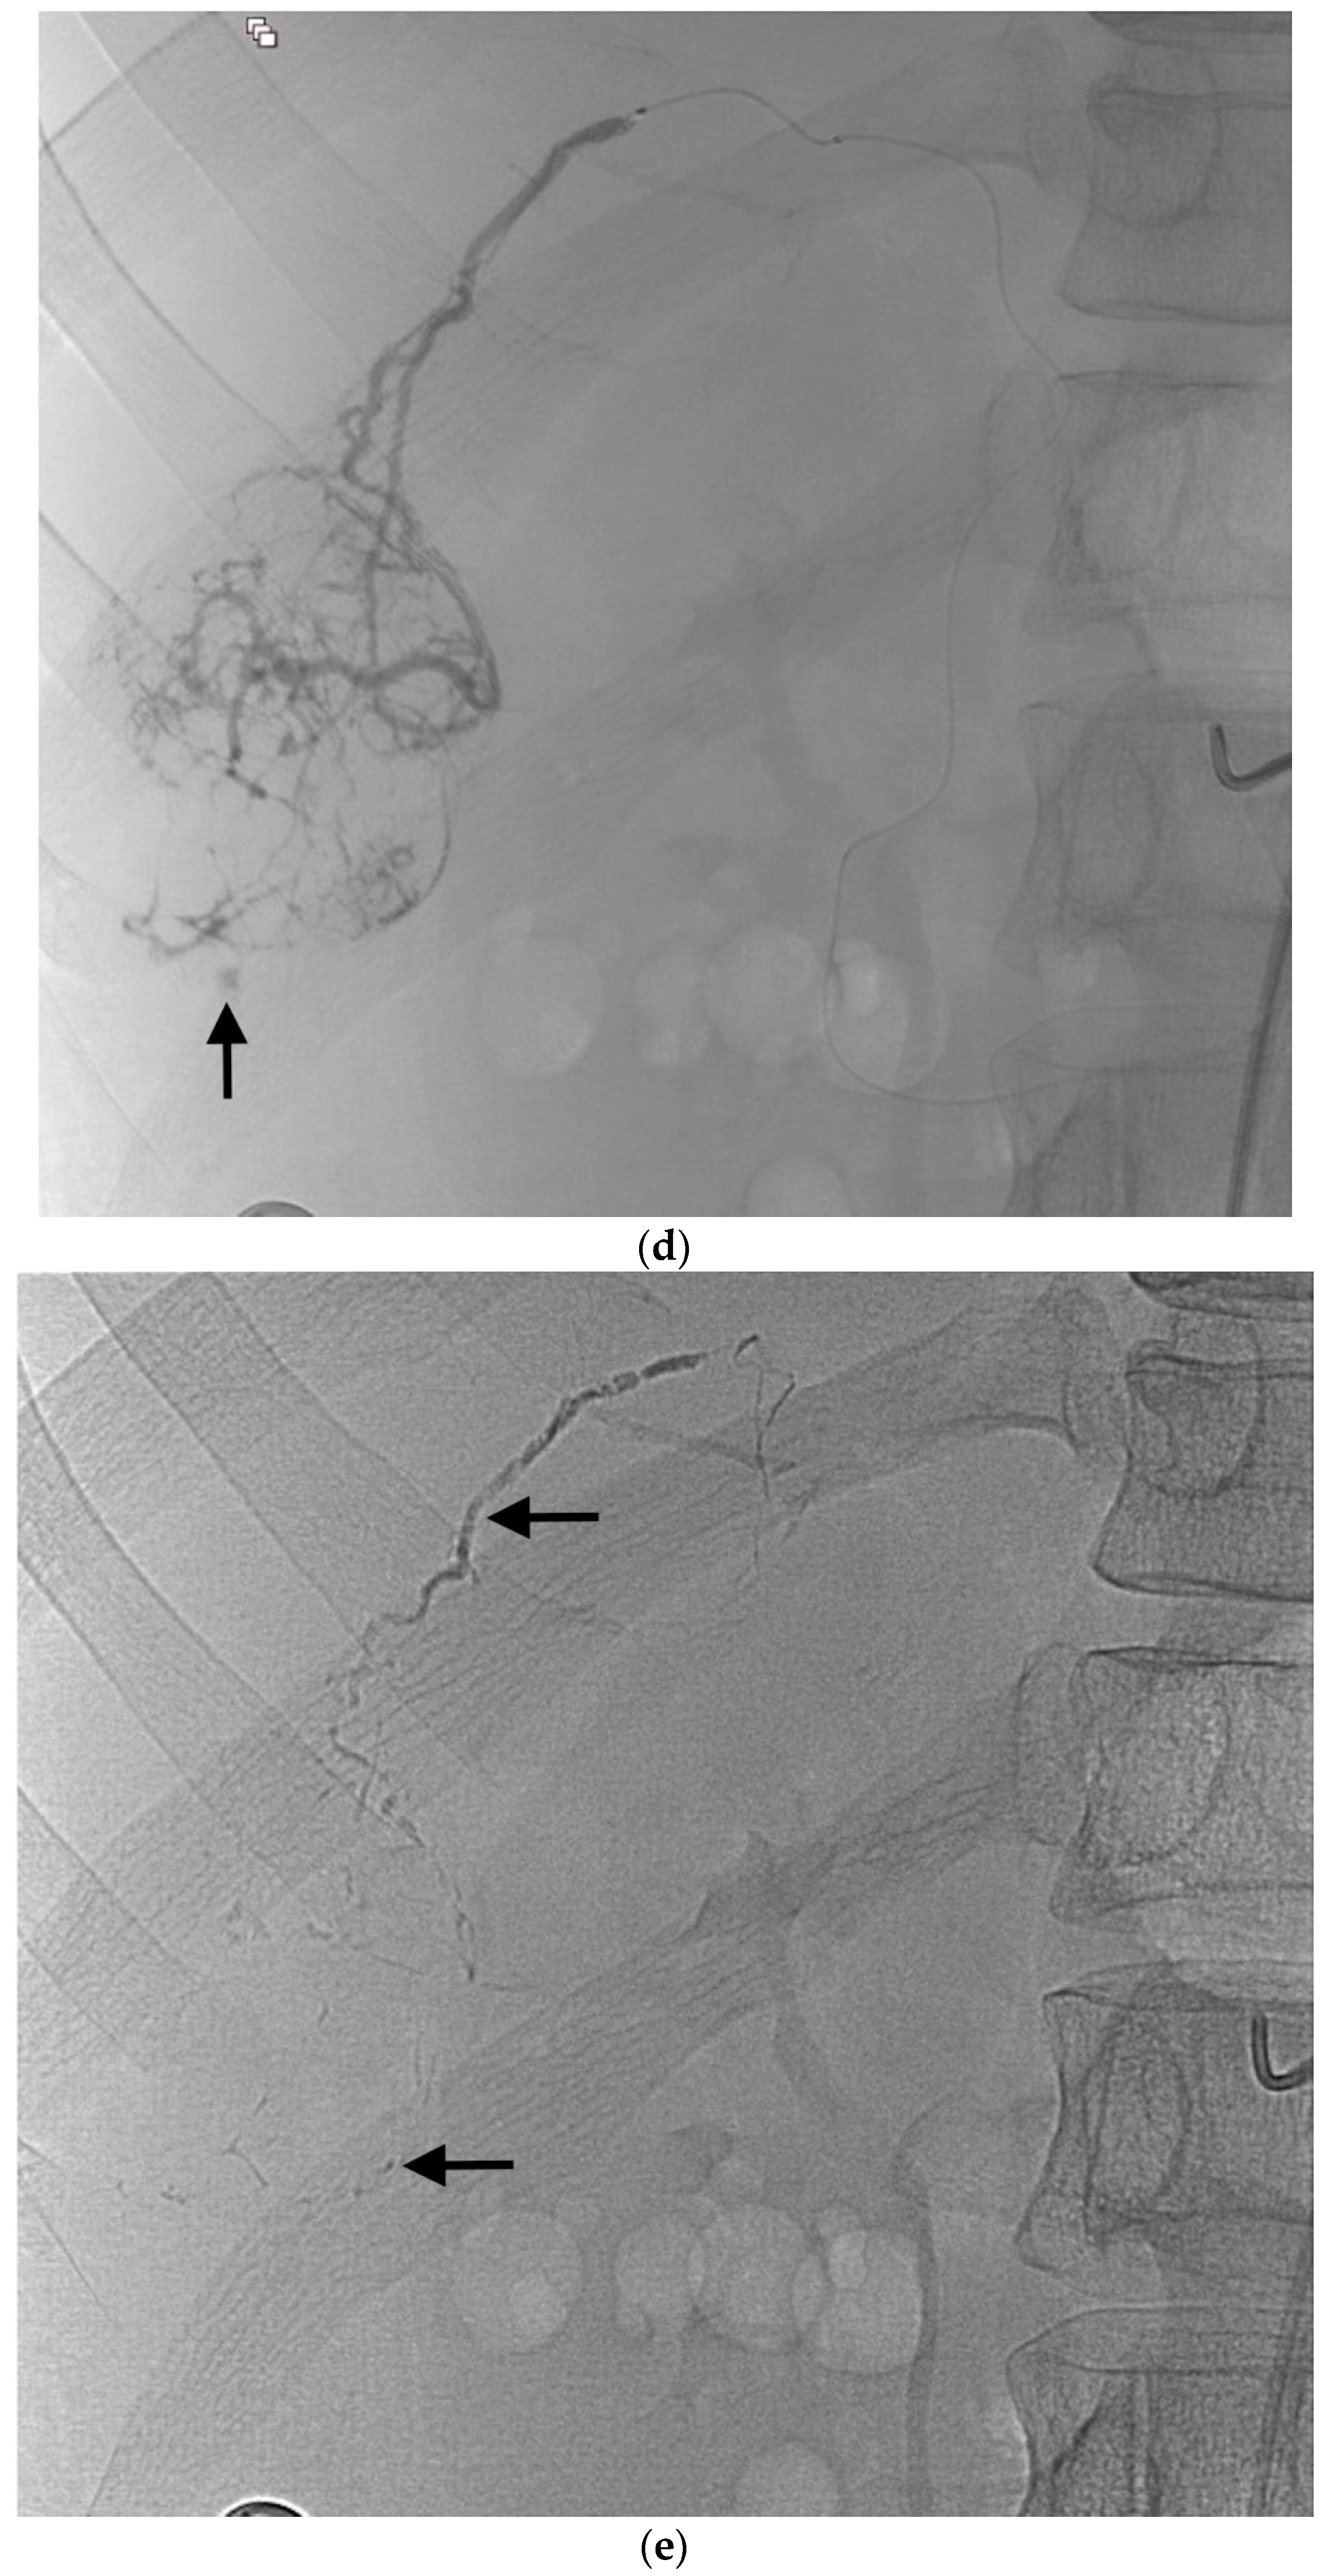

2.4. Selective Arterial Embolization Procedure